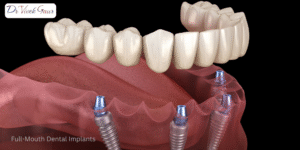

When it comes to oral rehabilitation, full-mouth dental implants have emerged as one of the most reliable and life-changing treatment options

When patients face multiple missing or damaged teeth, the most effective and long-lasting solution is full mouth dental implants. Unlike

Full-mouth rehabilitation is far more than just replacing missing teeth; it is a complex restoration process involving the jawbone, gums,